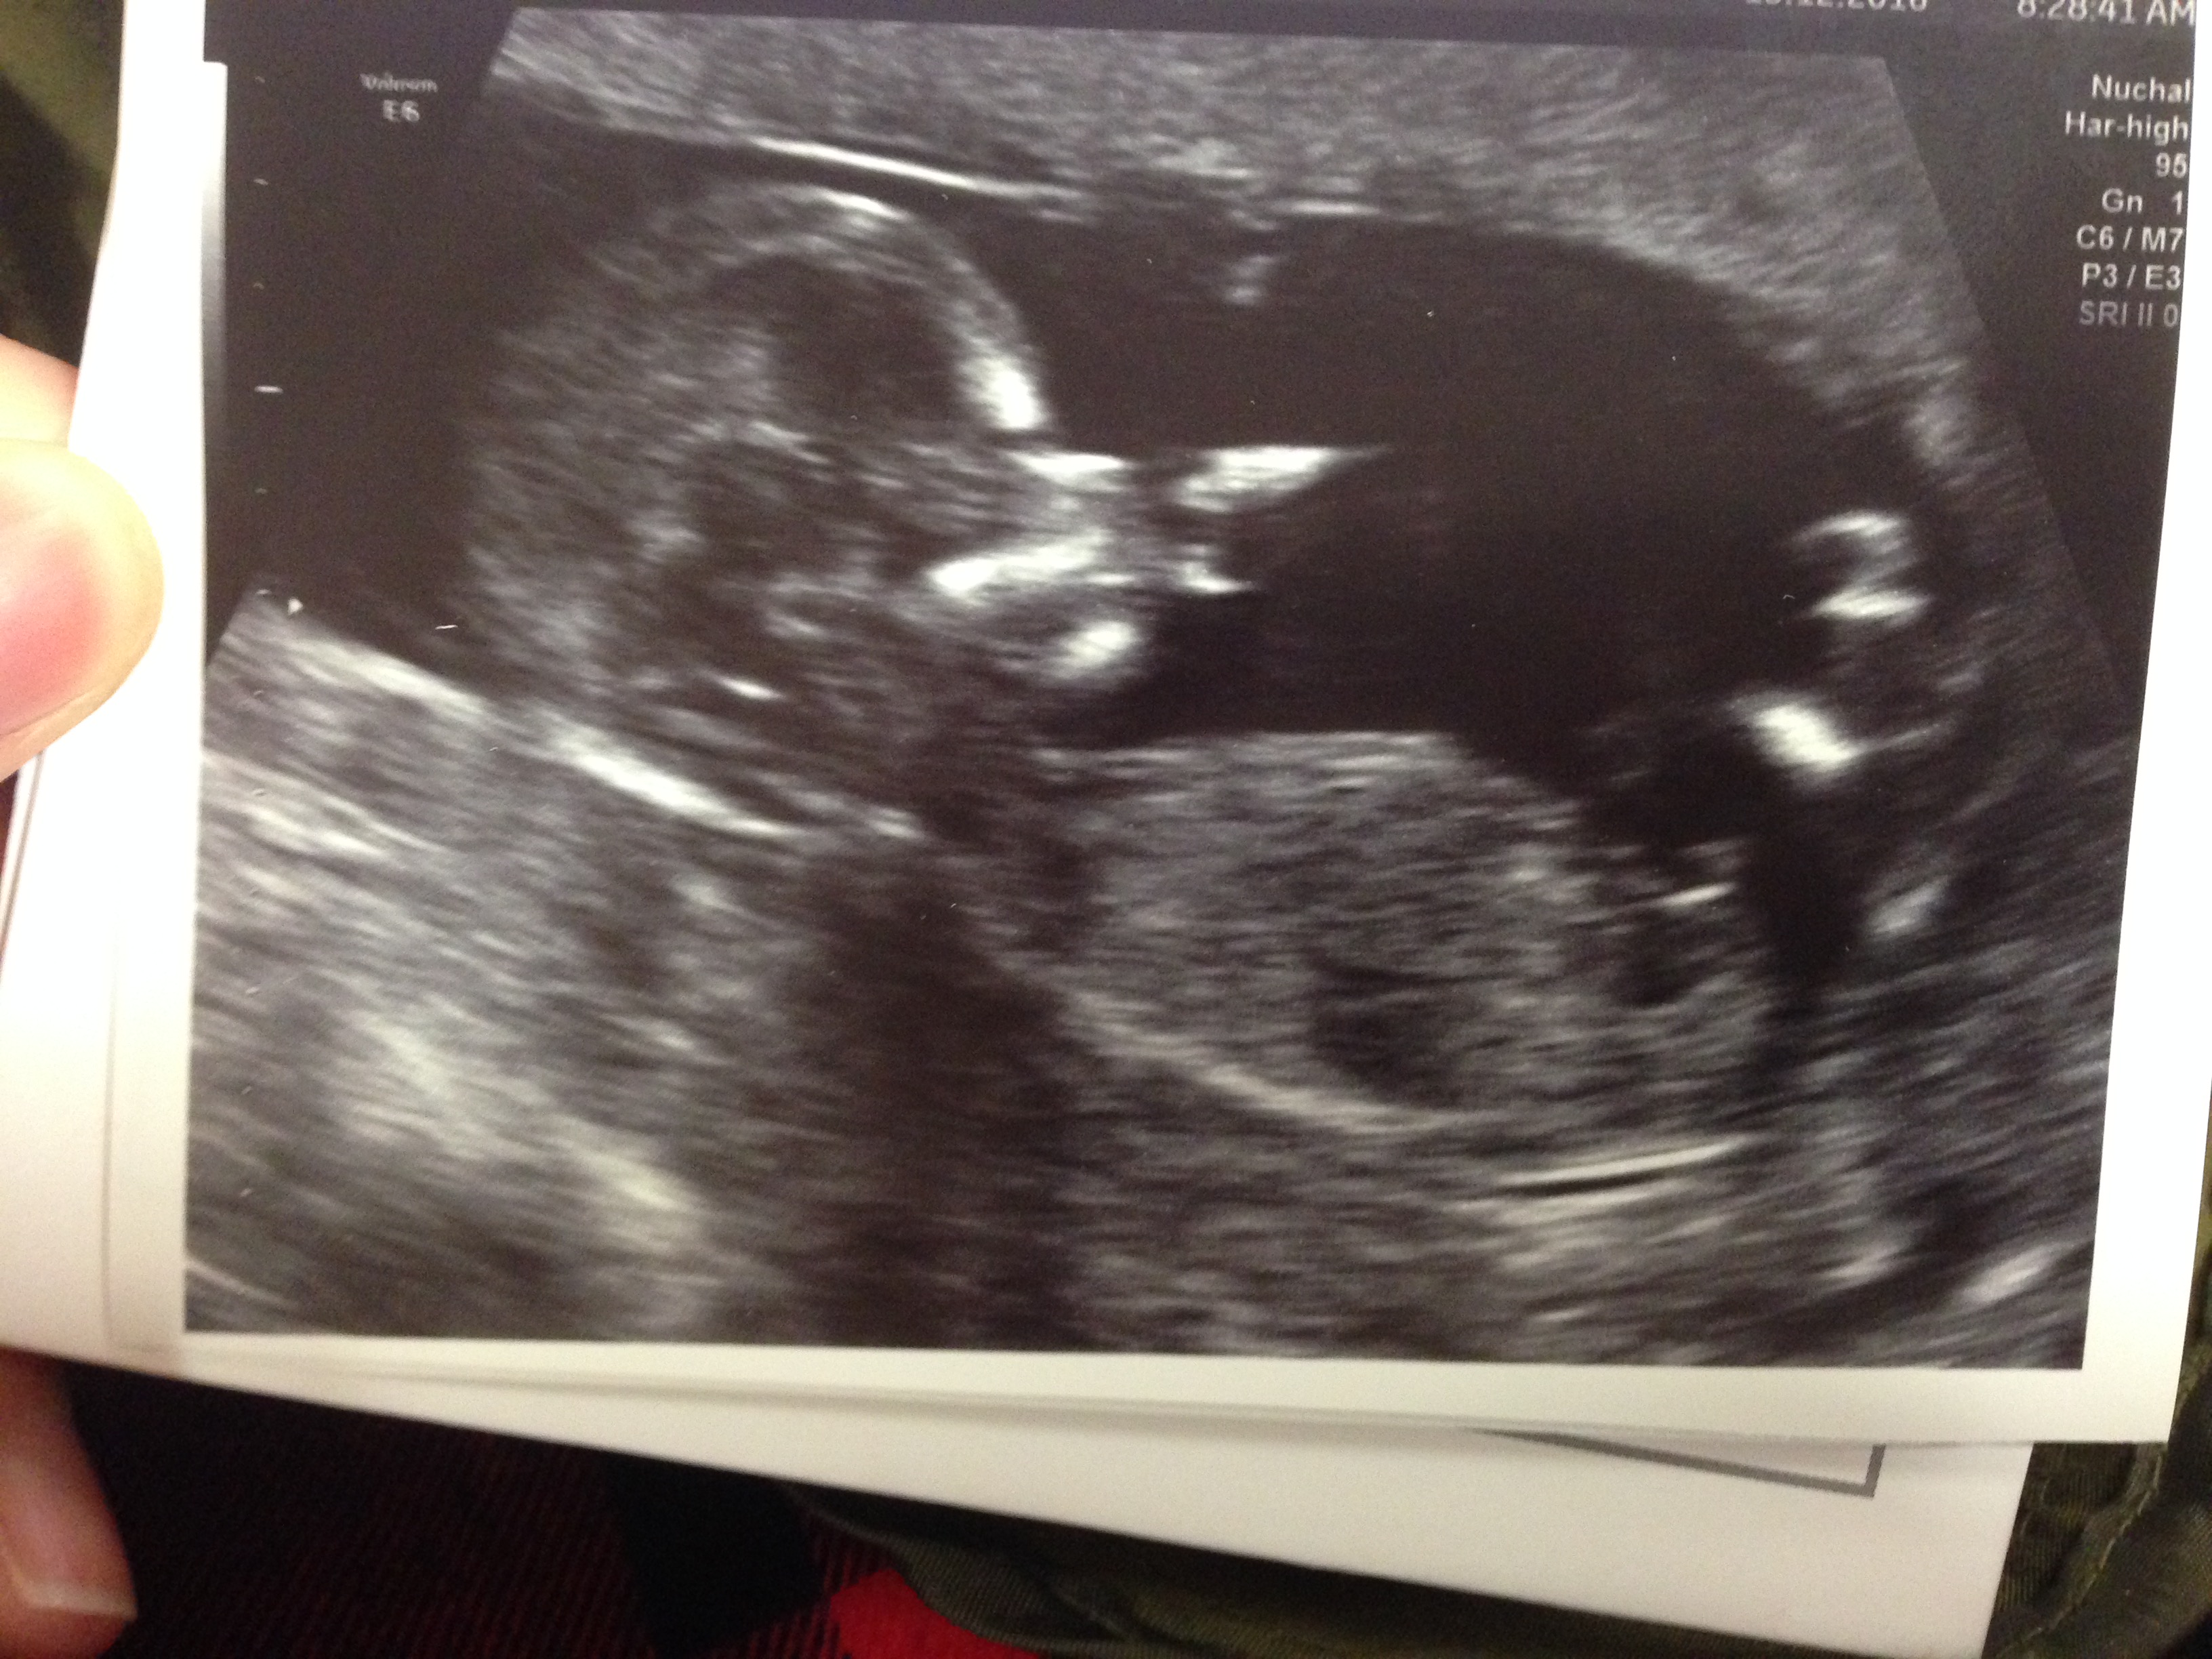

This is the only picture they let me buy.

My hospital apparantly only does 1 photo annoying.

Would love some guesses

I do see a boy nub i believe so i am expecting you will hear boy...go see your adorable baby boy at 16 weeks if you can..you and hubby can bond, get 100% confirmation and fall even more in love with your little one without the rushed scan a doctor will do at 20 weeks anyhow.. he looks like he is eating his hand in these pictures...he is just too sweet.